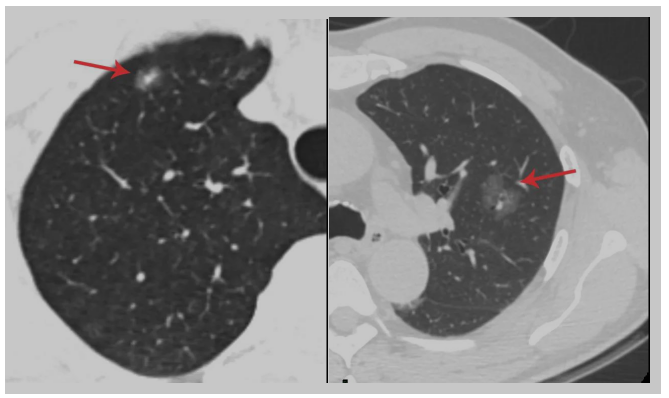

肺结节是影像学上的一个术语,其定义为直径≤3 cm的局灶性、类圆形、密度增高的实性或亚实性肺部阴影,可为孤立或多发。肺结节按密度分为纯磨玻璃结节、部分实性结节、实性结节。

打个比方,从CT上看这些结节相当于纯沙子、有石头的沙子、石头。它的本质可能是炎症、出血、组织增生,甚至是癌前病变。从恶性概率来看:部分实性结节>磨玻璃密度结节>实性结节。